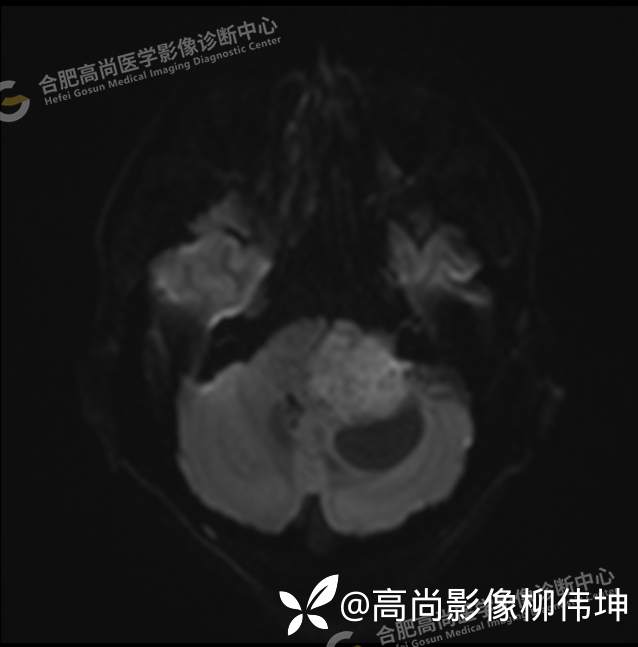

颅脑MRI平扫+增强示:双侧大脑半球对称,左侧桥小脑角区可见一团块状异常信号影,边界尚清,病灶与小脑幕宽基底附着呈“D”字征,上缘指状伸入幕缘上生长,病灶大小约43mmx42mmx36mm,其内信号不均,T1WI呈等低信号,T2WI呈混杂等高信号;FLAIR呈高信号,内可见条状低信号影,DWI呈稍高信号,ADC呈低信号,弥散轻度受限,病灶后方左侧小脑半球区可见一大小约33mmx16mm的弧形长T1长T2信号影,FLAIR呈低信号,其周围可见片状高信号影,相邻桥小脑角增宽。脑桥、小脑蚓部,小脑半球、第四脑室、环池受压变形,向右侧偏移,四脑室明显变窄,增强扫描病灶可见不均匀明显强化,邻近脑膜可见线样强化改变。其后方囊性灶未见异常强化。邻近骨质未见明显异常信号。左侧内听道显示正常;左侧中耳乳突内可见不规则性长T1长T2信号影。余脑实质内未见局灶性信号异常。双侧侧脑室及第三脑室体积增大,中线结构居中。矢状面示垂体形态大小正常,未见局灶性异常信号。

1.左侧桥小脑角区占位伴周围囊变,轻度梗阻性脑积水;考虑左小脑幕脑膜瘤。